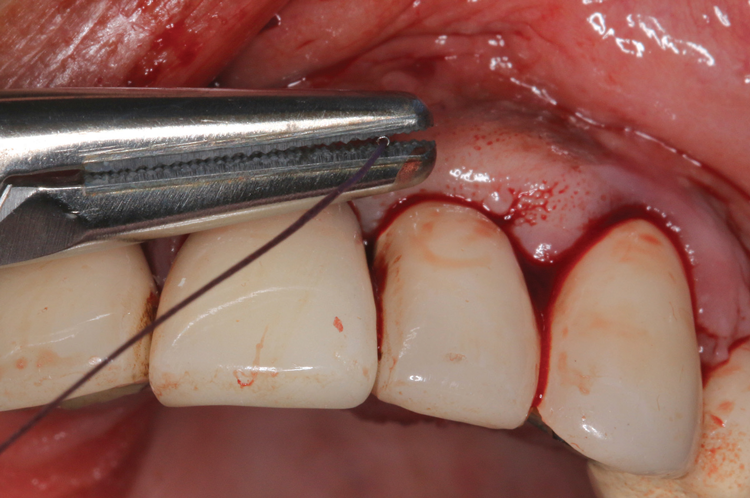

There are many grafting materials available today, including allografts (from a human source), xenografts (from another species), and alloplasts (from synthetic materials).23 Following debridement and sterilization of the apical lesion, the site was grafted with a mineralized cortical/cancellous bone allograft material (Newport Biologics Mineralized Cortico/Cancellous Allograft Blend, Glidewell Direct [alternatively: OSSIF-I sem Mineralized Cortical/Cancellous Bone Allograft, Surgical Esthetics; enCore® 50/50 Cortical & Cancellous Allograft, Osteogenics]). The material was packed firmly around the entire implant body but not crushed (Figure 7). Next, a resorbable collagen membrane (Newport Biologics Resorbable Collagen Membrane 3-4, Glidewell Direct [alternatively: Bio-Gide®, Geistlich Biomaterials; BioMend®, Zimmer Biomet]) was trimmed to extend approximately 2-mm beyond the borders of the defect and then passively positioned to serve as a barrier against epithelial growth during the healing and remodeling phase (Figure 8). A sling suture technique using polyglactin 910 suture was then used to reposition the envelope reflection (Figure 9 through Figure 11). Polyglactin 910 suture is a smooth, synthetic, absorbable, braided suture made of polyglycolic acid that is broken down over time by hydrolysis. This suture material reduces the inflammatory response that can be observed with other suture materials.

(9.) A sling suture technique was used to reposition and secure the reflected tissue.

Figure 9

(10.) A sling suture technique was used to reposition and secure the reflected tissue.

Figure 10

(11.) A sling suture technique was used to reposition and secure the reflected tissue.

Figure 11